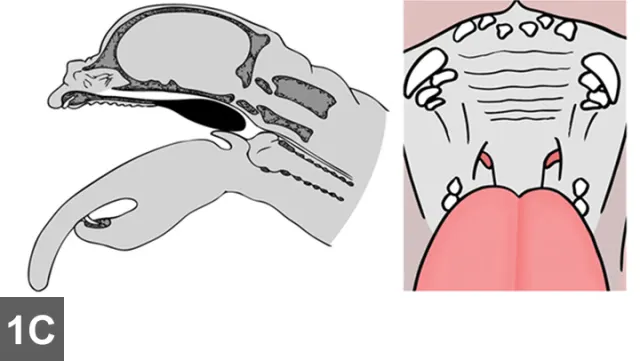

Place the dog in sternal recumbency. Restrain the head with the mouth open and the tongue gently pulled and fixed rostrally (Figures A, B, C).